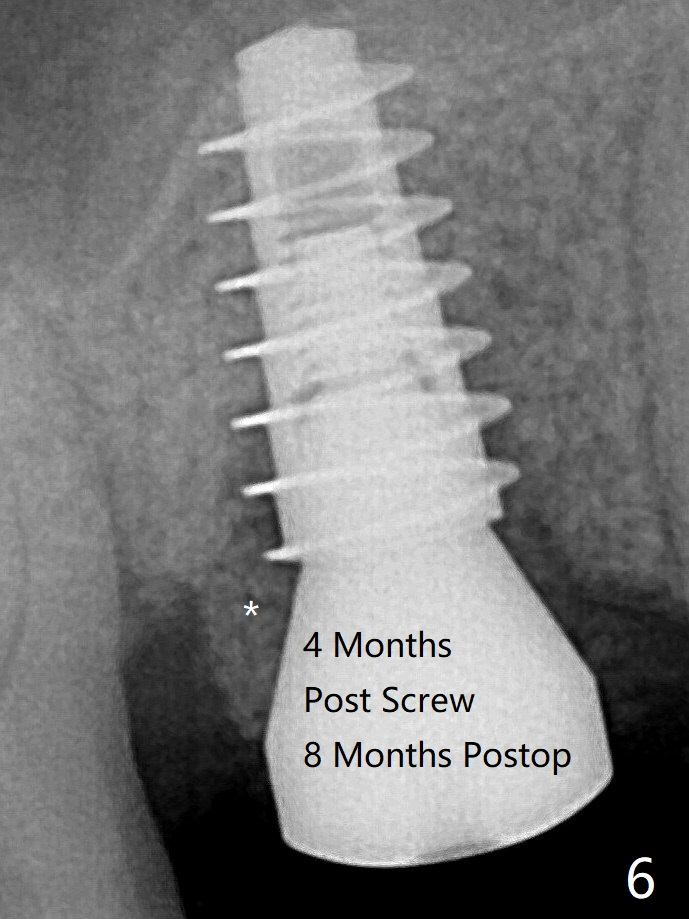

愈合帽放置4个月,伤口还没有完全愈合,翻瓣后发现远中螺纹表面肉芽组织覆盖,去除后者,第一螺纹暴露。放置愈合基台后,从颊侧往远中缺陷填入骨粉(图六:*),缝合,覆盖树脂敷料。